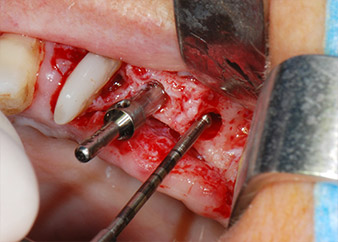

имплантологичен мотор

Фиг. 8: Препарация на имплантологичното ложе близо до пода на максиларния синус в позиция 25, изпълнена с новия имплантологичен мотор.

Имплантологичното ложе е подготвено в позиции 25 и 26 с ротиращи инструменти, използвайки обратен наконечник 20:1 с усъвършенстван и мощен имплантологичен мотор (Implantmed, W&H) (Фиг. 8).

Следващата препарация близо до синуса отново е извършена с пиезохирургичен накрайник (Piezomed, накрайник S2).